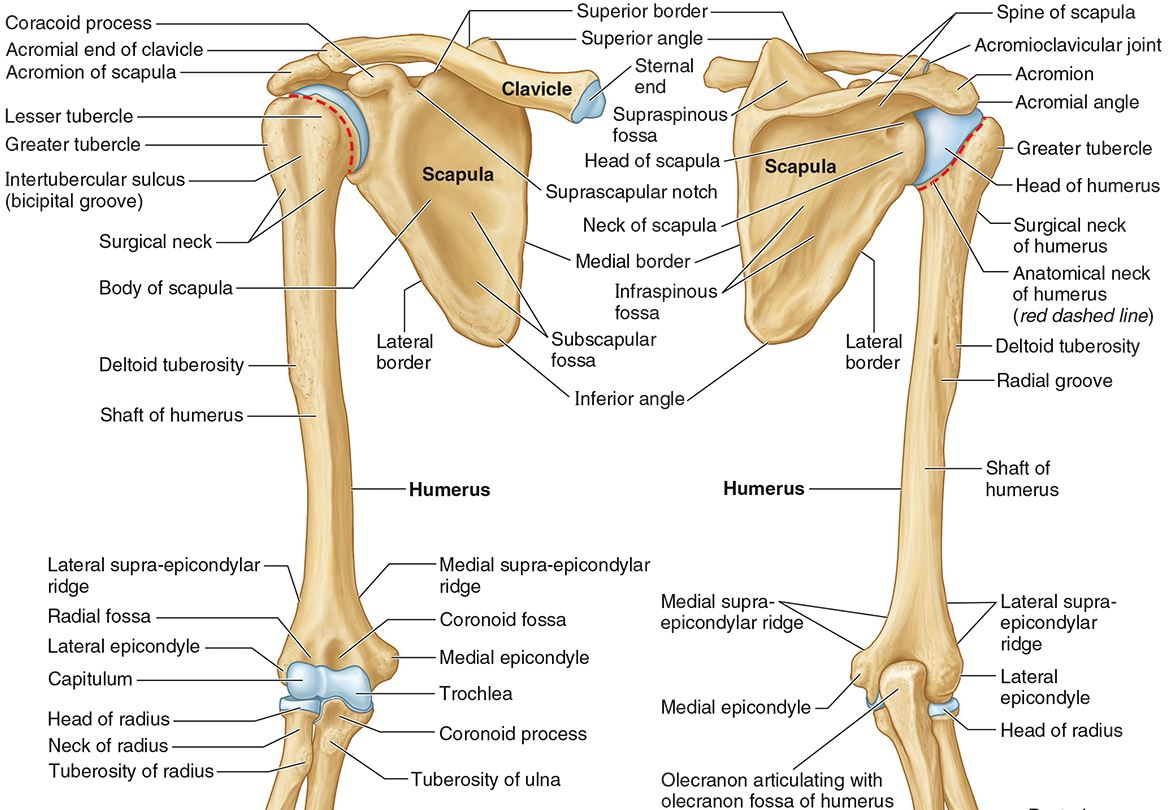

What is the only bone in the upper arm?

The humerus

What part of the humerus is this?

The head of the humerus articulates with the scapula at the glenohumeral joint.

What part of the humerus is this?

The anatomic neck is an indentation distal to the head and provides an attachment for the fibrous joint capsule of the glenohumeral joint.

What part of the humerus is this?

The greater tubercle lies lateral and distal to the anatomic neck.

What part of the humerus is this?

The lesser tubercle lies on the anterior/medial side of the humerus, just distal the anatomic neck.

What part of the humerus is this?

The intertubercular (bicipital) groove lies between the greater and lesser tubercles.

What part of the humerus is this?

The surgical neck is a narrow area distal to the tubercles. It is a common site for proximal humerus fractures.

What part of the humerus is this?

The humeral shaft features the deltoid tuberosity laterally for the distal insertion of the deltoid muscle.

What part of the humerus is this?

The radial groove is an oblique depression that contains the radial nerve and deep brachial artery.

Which parts of the humerus is this?

The medial and lateral epicondyles are distal prominences to which many forearm tendons attach, near the elbow joint.

Which parts of the humerus is this?

The medial and lateral supracondylar ridges extend superiorly from the medial and lateral epicondyles.

Which parts of the humerus is this?

The trochlea and the capitulum (the condyles) are the most distal surfaces of the humerus, where it articulates with the forearm bones at the elbow joint

What part of the humerus is this?

The olecranon fossa is a posterior depression above the trochlea that receives that olecranon process of the ulna

What part of the humerus is this?

The coronoid fossa is an anterior depression above the trochlea that receives that coronoid process of the ulna.